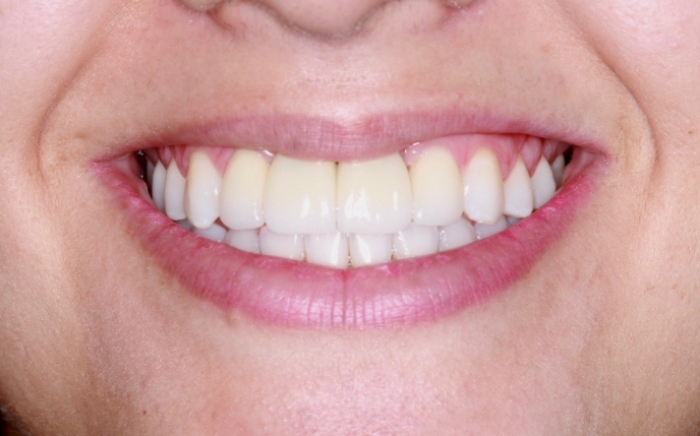

Imagem Inicial 2014